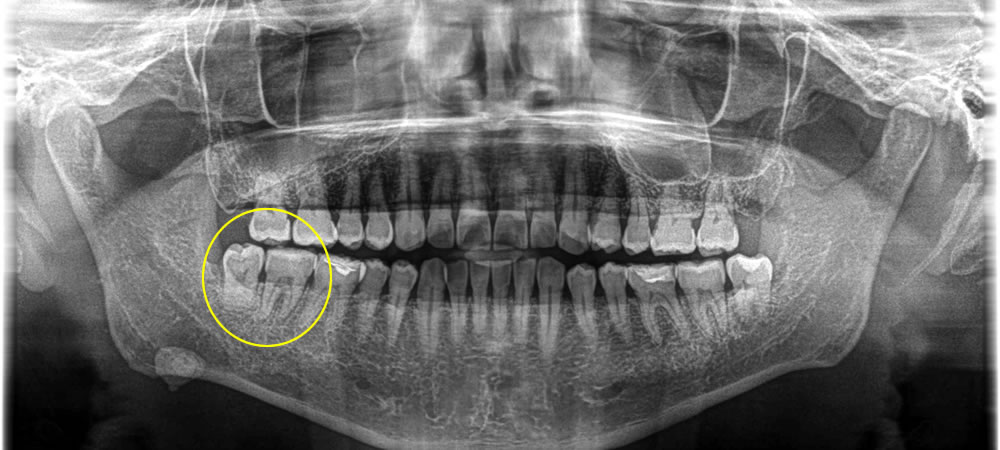

根尖性歯周炎の歯を抜歯即時埋入インプラントで治療した症例

こちらの患者さまは、右下奥歯が痛むとのことで来院されました。

レントゲン、CTで確認したところ、歯周病菌が原因で右下の親知らずと手前の歯が根尖性歯周炎になっていることが確認できました。

患者さまは「抜歯は避けたい」とのことでしたので、一先ず咬合調整を行い経過を観察しました。しかし、改善がみられませんでしたので、患者さまと相談して抜歯後にインプラント治療で咬み合わせを回復する計画を立てました。